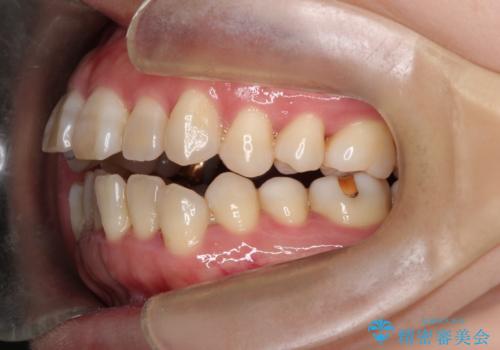

このケースでは非抜歯にて奥歯を後方に移動させる事で前歯の突出を改善するスペースを作り出していますが、これはマウスピースと顎間ゴムの併用によるもので、患者様のご協力の賜物と言えます。

深い噛み合わせについてはシミュレーション上の結果と、予期される実際の歯の移動量とを考慮し、特殊なセットアップを行う事で望ましい結果を得ることができました。

治療途中でリファインメントという追加のマウスピースを製作する手順を行っていますが、その際に上下の正中を合わせたいとの要望があったため、追加シミュレーションの際に追加でセットアップを施しましたが、無事、上下の正中もご要望通りに改善しています。

使用した装置はマウスピースと顎間ゴムのみです。ワイヤーやマイクロインプラントなど補助装置の使用はありません。